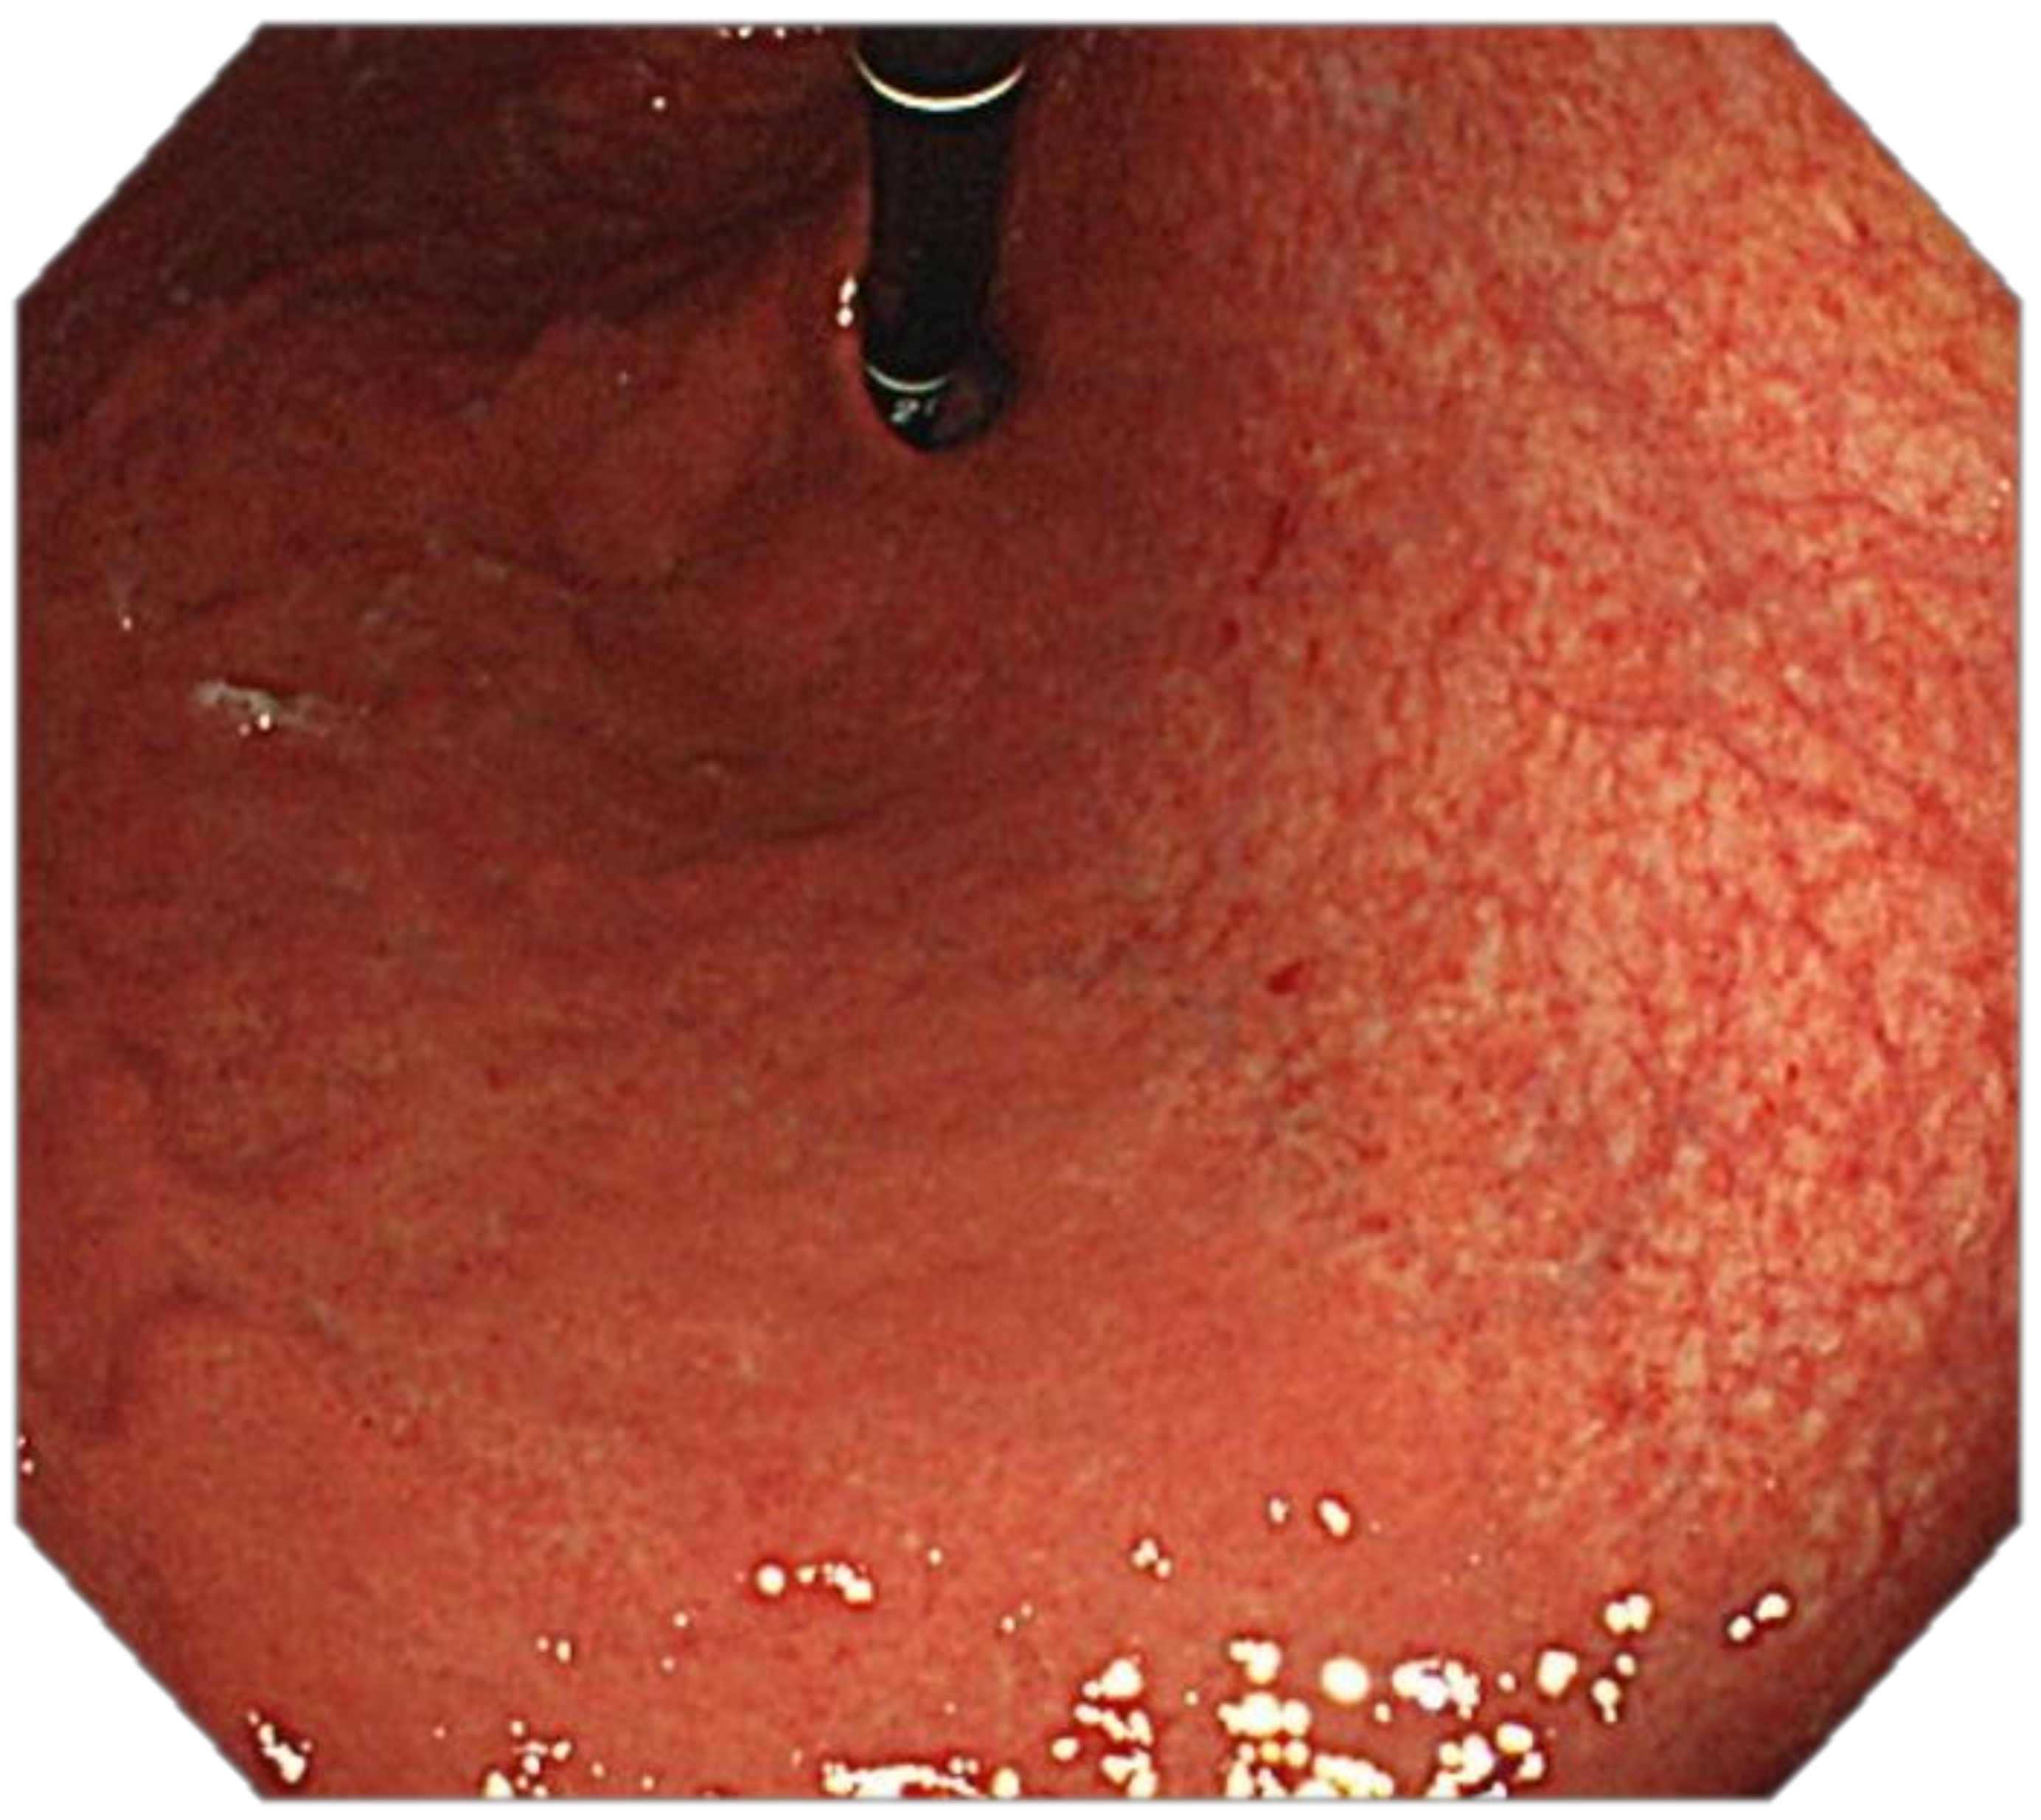

Optimal mucosal visualisation should be obtained through a combination of air insufflation, aspiration and the use of mucosal cleansing techniques with mucolytic and defoaming agents (e.g., N-acetylcysteine and simethicone) [157], see Figure 8, Figure 9, Figure 10, Figure 11, Figure 12, Figure 13, Figure 14. Despite progress made to date, premalignant lesions and early gastric cancer are still being missed [191,192]. A meta-analysis of 22 studies estimated a rate of missed gastric cancer at endoscopy of 9.4% [193]. Missed cancers were located mainly in the gastric body. Younger age (<55 years), female gender, marked gastric atrophy, gastric adenoma or ulcer, and inadequate number of biopsies were reported as predictive factors for diagnostic failure [193].

Our recommendation for daily routine practice is: (1) to use high-resolution white-light gastroscopes with magnifying NBI; (2) to achieve optimal mucosal visualisation with mucolytic and defoaming agents; (3) to keep minimal inspection time of 7 min.; (4) to obtain index images after a careful inspection (5) to take targeted biopsies of all suspicious or clearly pathological lesions; (6) to take multiple biopsies according to the protocol of the British Society of Gastroenterology (BSG) if suspicion of gastric atrophy and/or gastric intestinal metaplasia arise [113].